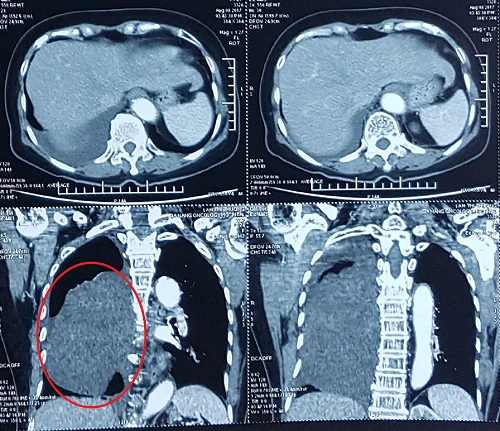

Khối u trong người bệnh nhân T có kích thước 15x8 cm.

Trước đó, sau một thời gian dài xuất hiện triệu chứng khó thở, tức ngực, bà Lâm Thị T. (74 tuổi) đến khám tại BV Ung bướu Đà Nẵng. Tại đây, các bác sĩ phát hiện trong người bệnh nhân có một khối u lớn ở trung thất, chèn vào phổi làm tắc đường hô hấp, chèn lệch tim…